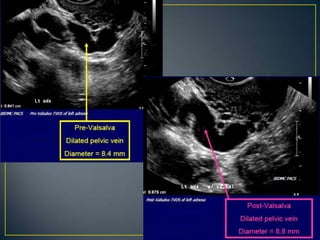

• Pelvic Congestion Syndrome postulated as cause of

chronic pelvic pain

• Venography is the gold standard

• However, ultrasound can still be used for diagnosis

• Dilated ovarian vein > 5 mm

• Tortuous veins around ovary and uterus (> 5mm)

• Venous plexus crossing from one side to another

• Change of flow direction with Valsalva maneuver

• Increase in size of veins with Valsalva maneuver

• Pelvic CongestionSyndrome postulated as cause of chronic pelvic pain • Venography is the gold standard • However, ultrasound can still be used for diagnosis

• 67.

• Dilated ovarianvein > 5 mm • Tortuous veins around ovary and uterus (> 5mm) • Venous plexus crossing from one side to another • Change of flow direction with Valsalva maneuver • Increase in size of veins with Valsalva maneuver